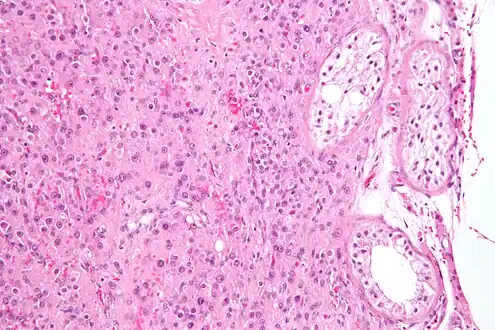

Section of a genital cord of the testis of a human embryo 3.5 cm long Intermediate magnification micrograph of a Leydig cell tumour, H&E stain

Leydig cells may grow uncontrollably and form a Leydig cell tumour. These may be hormonally active, i.e. secrete testosterone. The function of Reinke crystals is unknown, but they appear in the case of Leydig cell tumours.[5] They are found in less than half of all Leydig cell tumors, but when present, they may serve to confirm the diagnosis of a Leydig cell tumor.[10][11] No other interstitial cell within the testes has a nucleus or cytoplasm with these characteristics, making identification relatively easy.

While any age is susceptible to a Leydig cell tumour, Leydig cell tumours are more common in people aged 5 to 10 and 30 to 35.[12] A Leydig cell tumour in a child usually causes precocious puberty.[12] About 10% of boys with the tumour have gynecomastia.[12] Although a Leydig cell tumour is always benign in children, it is malignant in 10% to 15% of adults.[12] It is the most common testicular cancer of non-germ cell origin.[13]